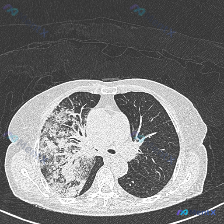

刚整理了一份很典型的胸部CT读片病例,核心是弥漫性肺病变的典型征象——铺路石征,把整个分析思路整理出来和大家一起讨论。 病例影像核心信息 本次分析的是胸部CT肺窗横断面图像,核心异常是空域混浊(Airspace opacity),详细影像特征如下: 1. 整体评估:双肺透亮度明显降低,呈弥漫性密度增...

整理到一份胸部CT肺窗横断面的影像分析,先抛出来大家讨论下第一思路。 核心影像表现: - 双肺弥漫性病变,以磨玻璃影(GGO)和网格状改变为主 - 部分区域呈「铺路石征」样改变(GGO 背景上叠加小叶间隔增厚),左肺上叶前部及双肺后部明显 - 可见支气管充气征及部分支气管壁增厚,肺血管纹理增粗 -...

整理到一份胸部CT的肺窗影像分析资料,先不说临床背景,仅看影像表现: 核心影像表现: - 双肺弥漫性磨玻璃密度影(GGO),以外周及胸膜下区域为主 - 磨玻璃影背景上可见网格状影、小叶间隔增厚,部分区域呈典型「铺路石征」 - 左肺上叶前段可见斑片状实性与磨玻璃混杂密度影 - 伴双肺支气管血管束增粗、...

整理到一份胸部CT肺窗横断面的影像资料,先不放临床背景,纯看影像表现: 📌 核心影像表现: - 病变范围:双肺弥漫性分布,上叶、下叶均受累 - 密度改变:大范围磨玻璃影(GGO),伴局限性肺实变,可见空气支气管征 - 间质改变:磨玻璃背景下见细小网格影(提示铺路石征样改变) - 分布偏好:双肺外带及...

整理到一份胸部CT肺窗横断面的影像分析资料,先不看病史,只看影像表现: 核心异常: - 双肺弥漫、多发磨玻璃影(GGO),分布较对称 - 部分区域小叶间隔增厚,有「铺路石征」倾向 - 双肺后部(背侧/重力依赖区)可见斑片状融合实变,内有空气支气管征 - 胸膜、胸廓骨骼、纵隔(肺窗可见范围内)未见明显...